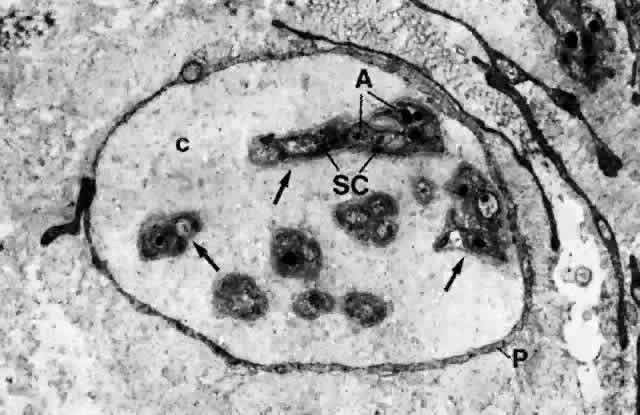

The nerve supply to the conjunctiva is derived entirely from the first division of the trigeminal nerve.10 The nerves to the lid supply most of the conjunctiva. These nerves comprise the infratrochlear branch of the nasociliary nerve, the lacrimal nerve, the supratrochlear and supraorbital branches of the frontal nerve, and the infraorbital nerve from the maxillary division of the trigeminal nerve. The limbal area is supplied by branches from the ciliary nerves. All nerves form a network in the conjunctiva and terminate either peripherally in various forms of specialized endings or on blood vessels and epithelial cells. The majority of nerve endings in the conjunctiva are free, unmyelinated nerve endings (Figs. 23 and 24). They form a sub-epithelial plexus in the superficial part of the substantia propria. Many of these fibers end on blood vessels, and others form an intraepithelial plexus around the base of epithelial cells and send free nerve endings between cells.10

Fig. 23. A nerve fiber bundle in conjunctival stroma (substantia propria) composed of several unmyelinated nerve fibers (arrows) surrounded by a layer of perineurium (P); there are also intervening collagen fibrils (c). Each unmyelinated nerve fiber is composed of axons (A) wrapped with Schwann's cells (SC). (× 13,700)